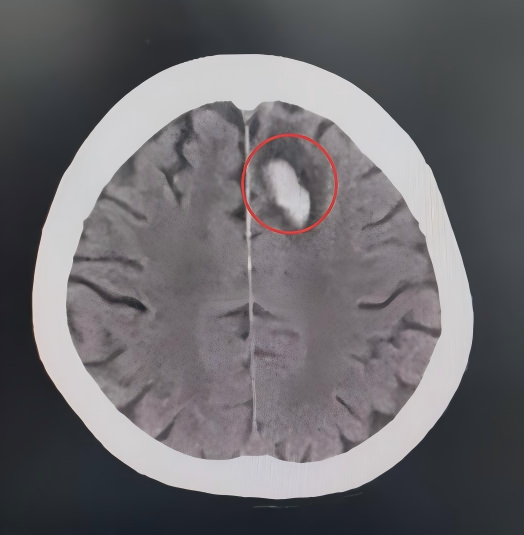

白色为创伤性颅内血肿,周边黑色为水肿

可以明显看到血肿和水肿范围在不断扩大

病情随时可能出现变化